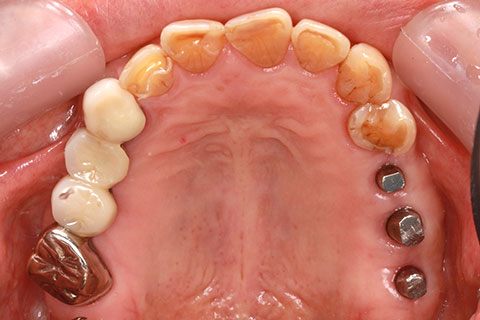

症例2

治療前

インプラント埋入時

治療後

- 年齢・性別

- 57歳男性

- 治療期間

- 3ヶ月

- 抜歯

- なし

- 治療費

- 154万円

- 備考

- 左上5.6.7 及び左下6.7欠損

- 治療内容

- 左上5.6.7と左下6.7欠損部にインプラント埋入

- 施術の副作用(リスク)

- オペによる知覚障害。インプラントによる歯肉炎。インプラント脱落。